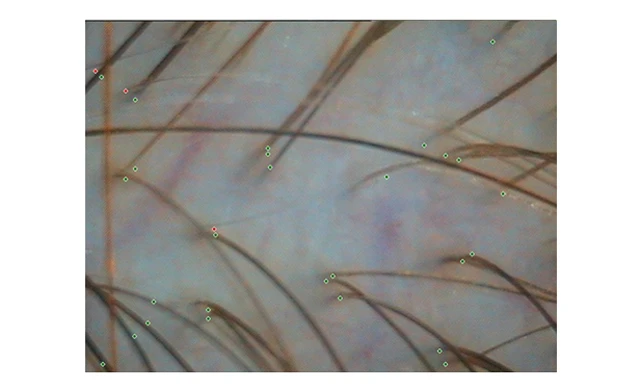

В двух зонах (теменной и затылочной), триммером сбриваются волосы на участке размером 8х8мм. Через 2-3 дня, когда волосы отрастут на 1 мм (в норме 0,3-0,4 мм в сутки) или останутся прежнего размера (анагеновые и телогеновые волосы соотвественно), участки подкрашиваются безаммиачным красителем для волос, и с помощью трихоскопа, подключенного к компьютеру, под х40-увеличением заносятся в специализированную компьютерную программу (Trichoscience).

Фототрихограмма при диффузном выпадении волос.

Анаг.-71%(дисп.14%) Тел. -28% (дисп.18%) плотность волос 262,55 на см. кв.

(норма 300±20/см?)

Анаг.-70%(дисп.11%) Тел.-30%(дисп.15%) плотность волос 140,21 на кв. см.

(норма 195±13/см?)